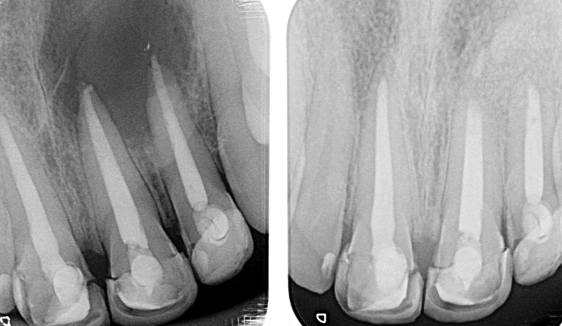

Fisuras

Los dientes fisurados muestran muchos tipos de síntomas, incluido el dolor al masticar, la sensibilidad a la temperatura o incluso la liberación de presión al morder. También es común que el dolor de dientes vaya y venga, lo que dificulta el diagnóstico de la causa del malestar.

La masticación puede causar el movimiento de las piezas fisuradas de su diente, y la pulpa dentro del diente se irrita. Al mismo tiempo, cuando se libera la presión de morder, la grieta puede cerrarse rápidamente, lo que produce un dolor agudo. Eventualmente, la pulpa se dañará y el diente dolerá constantemente, incluso cuando no esté masticando. Es posible que las grietas puedan provocar la infección del tejido pulpar, que puede extenderse al hueso y la encía que rodea el diente.

Diente fisurado tratable

Este tipo de fisura se extiende desde la superficie de masticación del diente y migra verticalmente hacia la raíz. En algunos casos, la grieta puede extenderse por debajo de la línea de las encías. Es posible que la grieta se extienda más hacia la raíz. El daño a la pulpa es común. En este caso, el tratamiento del conducto radicular suele ser necesario. Un diente roto que no se trata empeorará, lo que provocará la pérdida del diente. Por lo tanto, la detección temprana es esencial.